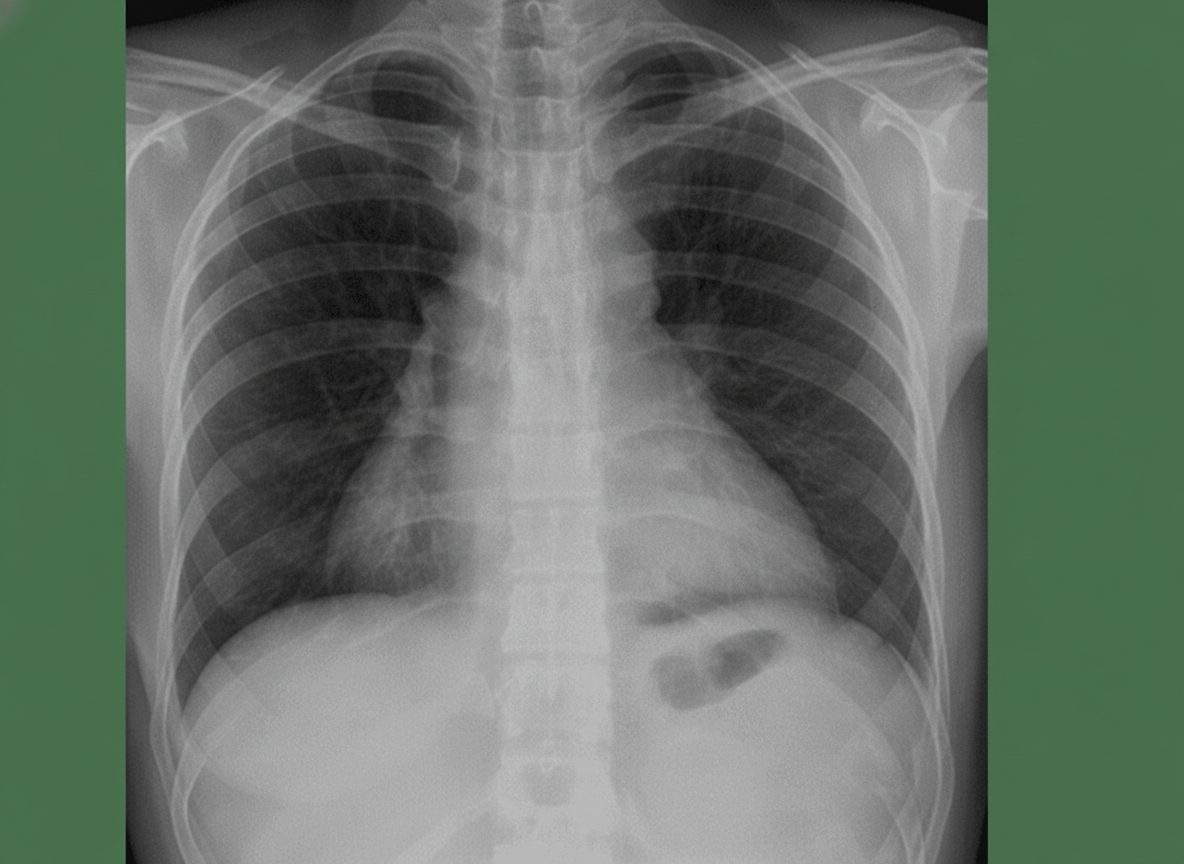

A 28-year-old man is brought to the emergency department with shortness of breath and chest pain, 35 minutes after he was involved in a high-speed motor vehicle collision. He was the helmeted driver of a scooter hit by a truck. On arrival, he is alert and oriented with a Glasgow Coma Scale rating of 14. His temperature is 37.3°C (99.1°F), pulse is 103/min, respirations are 33/min and blood pressure is 132/88 mm Hg. Pulse oximetry on room air shows an oxygen saturation of 94%. Examination shows multiple abrasions over his abdomen and extremities. There is a 2.5-cm (1-in) laceration on the left side of the chest. There are decreased breath sounds over the left base. Cardiac examination shows no abnormalities. The abdomen is soft and there is tenderness to palpation over the left upper quadrant. Bowel sounds are normal. His hemoglobin concentration is 13.6 g/dL, leukocyte count is 9,110/mm3, and platelet count is 190,000/mm3. A chest x-ray is shown. Which of the following is the most likely diagnosis?

A 50-year-old man presents with severe chest pain for a week. His pain increases with breathing and is localized to the right. He has tried over-the-counter medications at home, but they did not help. The patient has a 20-pack-year smoking history and currently smokes 2 packs of cigarettes daily, and he drinks 3 to 4 cans of beer daily before dinner. His temperature is 39.1°C (102.3°F), blood pressure is 127/85 mm Hg, pulse is 109/min, and respirations are 20/min. Respiratory examination shows dullness to percussion from the 7th rib inferiorly at the right midaxillary line, decreased vocal tactile fremitus, and diminished breath sounds in the same area. Chest radiograph is shown in the image. The patient is prepared for thoracocentesis. Which of the following locations would be the most appropriate for insertion of a chest tube?